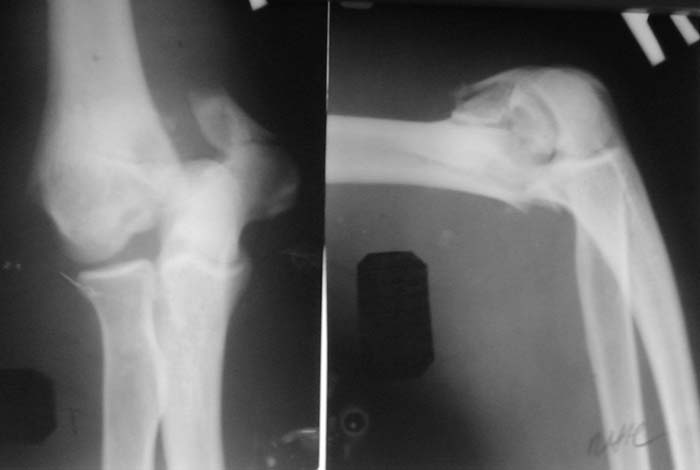

Солидарен с мнением обоих Александров (Челнокова и Рыкова): точную репозицию такого перелома вряд ли удастся выполнить закрыто. Даже во время открытого вмешательства это сделать непросто. Неслучайно предложен костно-пластический доступ с временным отсечением локтевого отростка. И по методу фиксации согласен с Александром Челноковым: 2 пластины. В качестве примера привожу рентгенограммы одного из наших пациентов с аналогичным повреждением.

С уважением, А. Золотов, Приморский край.